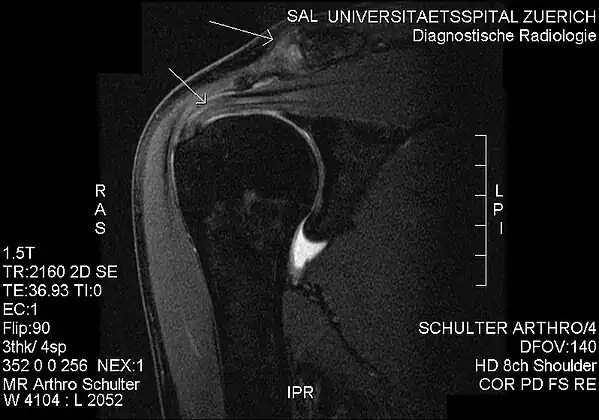

Imaging

Plain x-rays of the shoulder can be used to detect some joint pathology and variations in the bones, including acromioclavicular arthritis, variations in the acromion, and calcification. However, x-rays do not allow visualization of soft tissue and thus hold a low diagnostic value.[5] Ultrasonography, arthrography and MRI can be used to detect rotator cuff muscle pathology. MRI is the best imaging test prior to arthroscopic surgery.[5] Due to lack of understanding of the pathoaetiology, and lack of diagnostic accuracy in the assessment process by many physicians,[21] several opinions are recommended before intervention.